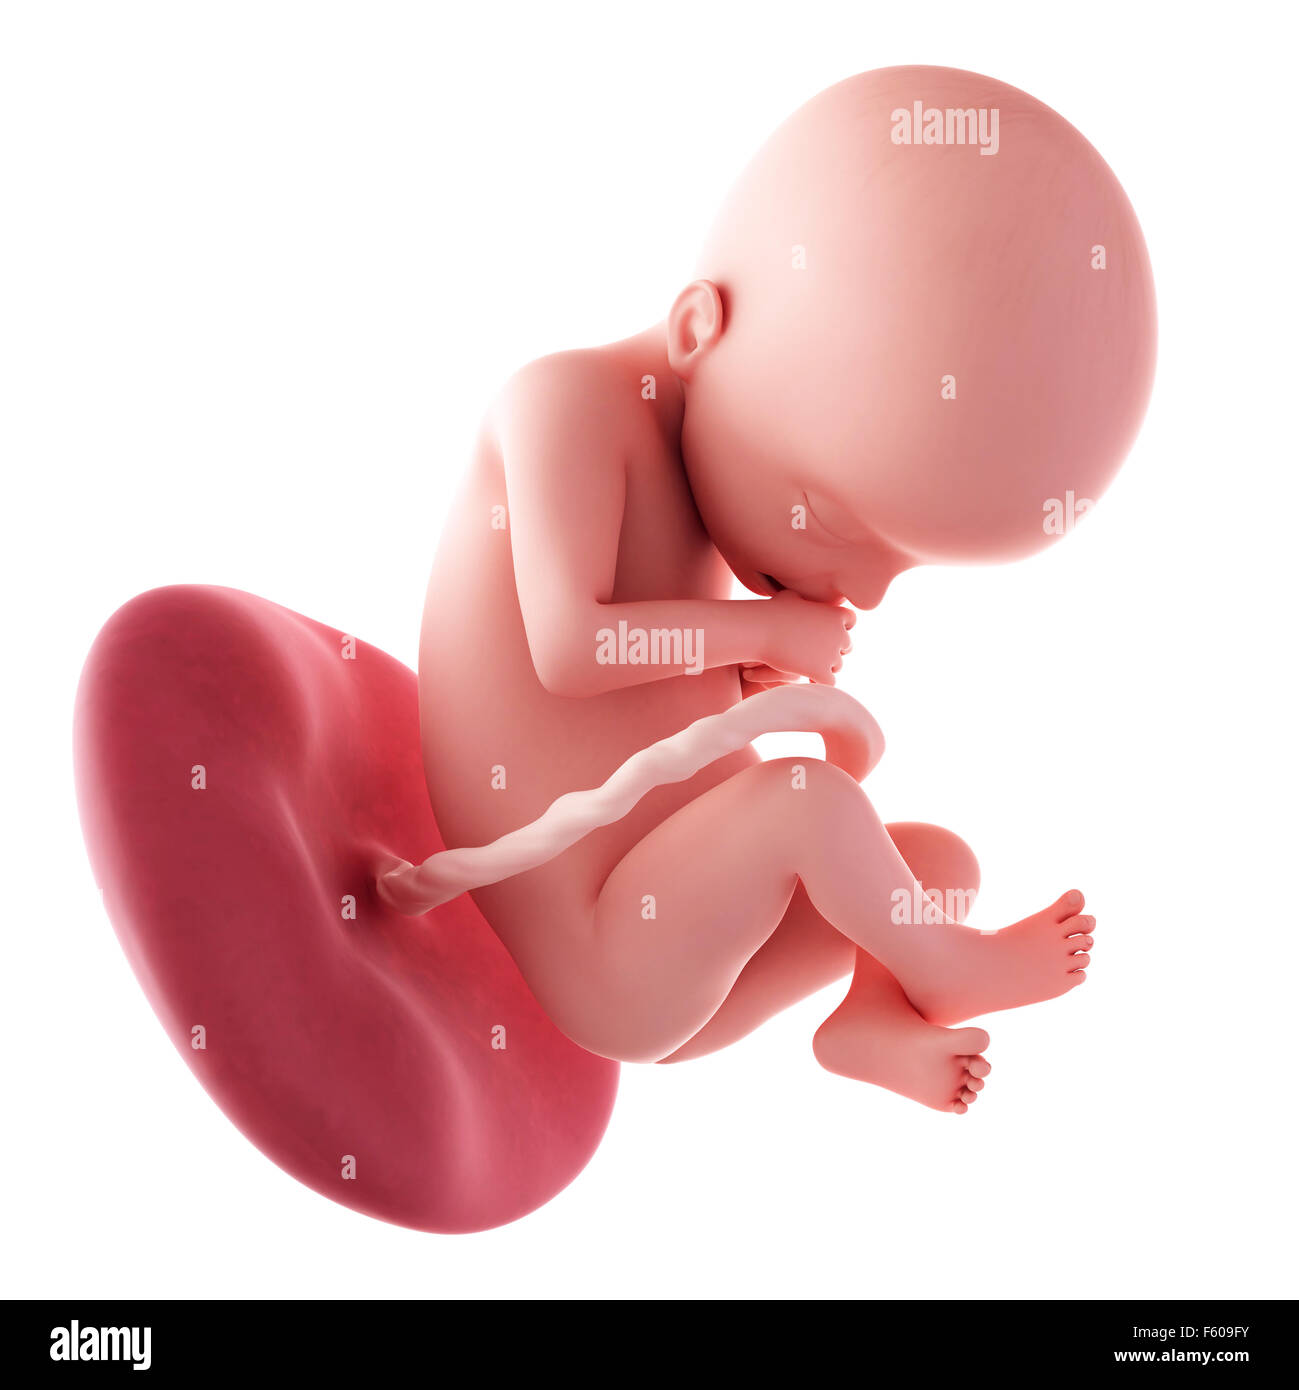

Una Settimana 22 Del Feto Illustrazione Di Stock Illustrazione Di Biologia 101127188

Settimana Feto Umano 22 Settimana Reso Feto 22 Accurato Illustrazione Medically Umano 3d Canstock

Eta Feto Umano 22 Settimane 3d Fondo Bianco Stock Photo 160556350